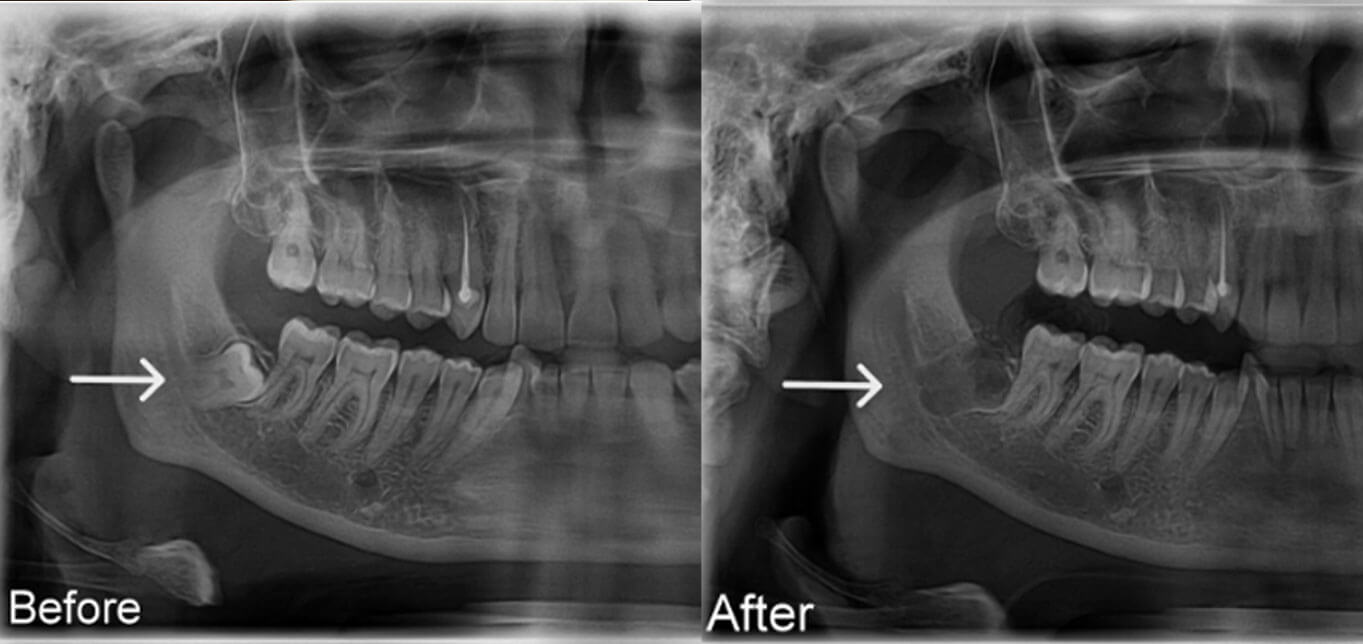

Bước 2: Chụp phim X-quang kiểm tra vị trí răng khôn

Đây là bước rất quan trọng giúp:

- Xác định chính xác vị trí và hướng mọc của răng khôn.

- Đánh giá khoảng cách đến các cấu trúc quan trọng như răng số 7, xoang hàm, dây thần kinh.

- Lập kế hoạch nhổ răng an toàn, hạn chế tối đa biến chứng.

Bệnh nhân được chụp phim, đánh giá kỹ lưỡng trước khi nhổ răng